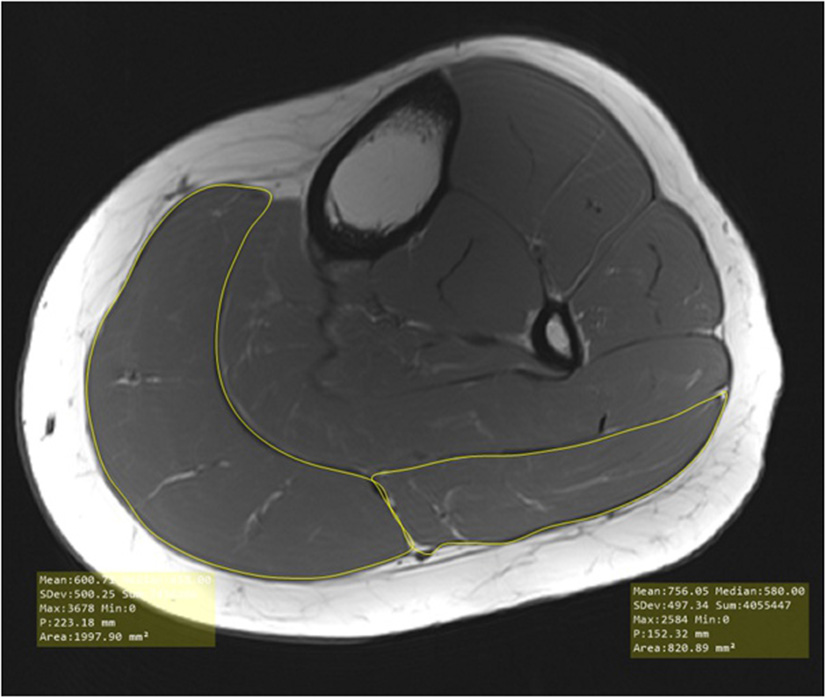

MRI was performed at the Neuroimaging Unit of the Carl von Ossietzky University of Oldenburg using a 3T Siemens Magnetom Prisma MRI with a T1-weighted turbo-spin-echo sequence (40 slices, slice thickness = 7 mm, TR = 1600 ms, TE = 14 ms, voxel size = 0.4 x 0.4 mm2, FOV = 150 x 150, distance factor = 20%, flip angle = 150°, TA = 8:16 min) with a combination of the body and spine coil. Each participant was placed on the back and the measurement was performed first on the left leg, immediately followed by the right leg. The evaluation of MRI images and therefore examination of MCSA was performed by bordering the fascia layers of the lateral and the medial head of the gastrocnemius (see Figure 2) with MicroDicom (Sofia, Bulgaria) by two investigators independently from each other and anonymized for participant and group. Examination of images started from the first image distal of the knee joint where a clear bordering of the muscle could be seen to the transition from the muscle to the tendon. For evaluation of MCSA the mean of the three highest MCSA values in the lateral and the medial head of the gastrocnemius were used to minimize potential error of location (Koppenhaver et al., 2009; Teyhen and Koppenhaver, 2011). Reliability of MRI measurements can be assumed as very high with r = 0.99 (Wirth et al., 2007; Wang et al., 2021).

Figure 2

Evaluation of muscle cross-sectional area in the medial and lateral head of the gastrocnemius.